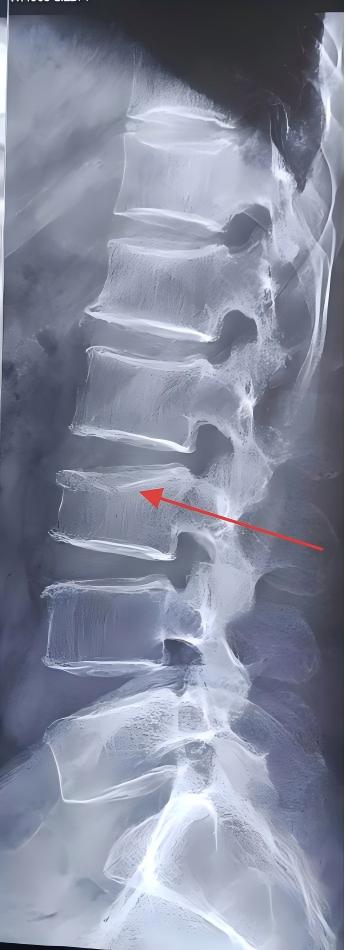

After careful consideration, I concluded that the patient's lower back pain might not be solely caused by the affected muscles but also by other factors. The patient, an elderly woman with a hunched posture, experienced acute onset after lifting heavy objects and denied any history of trauma. Given these circumstances, I suspected a vertebral compression fracture and recommended further examination at a higher-level hospital. The following day, the patient was diagnosed with compression fractures of the second and third lumbar vertebrae at a municipal hospital.